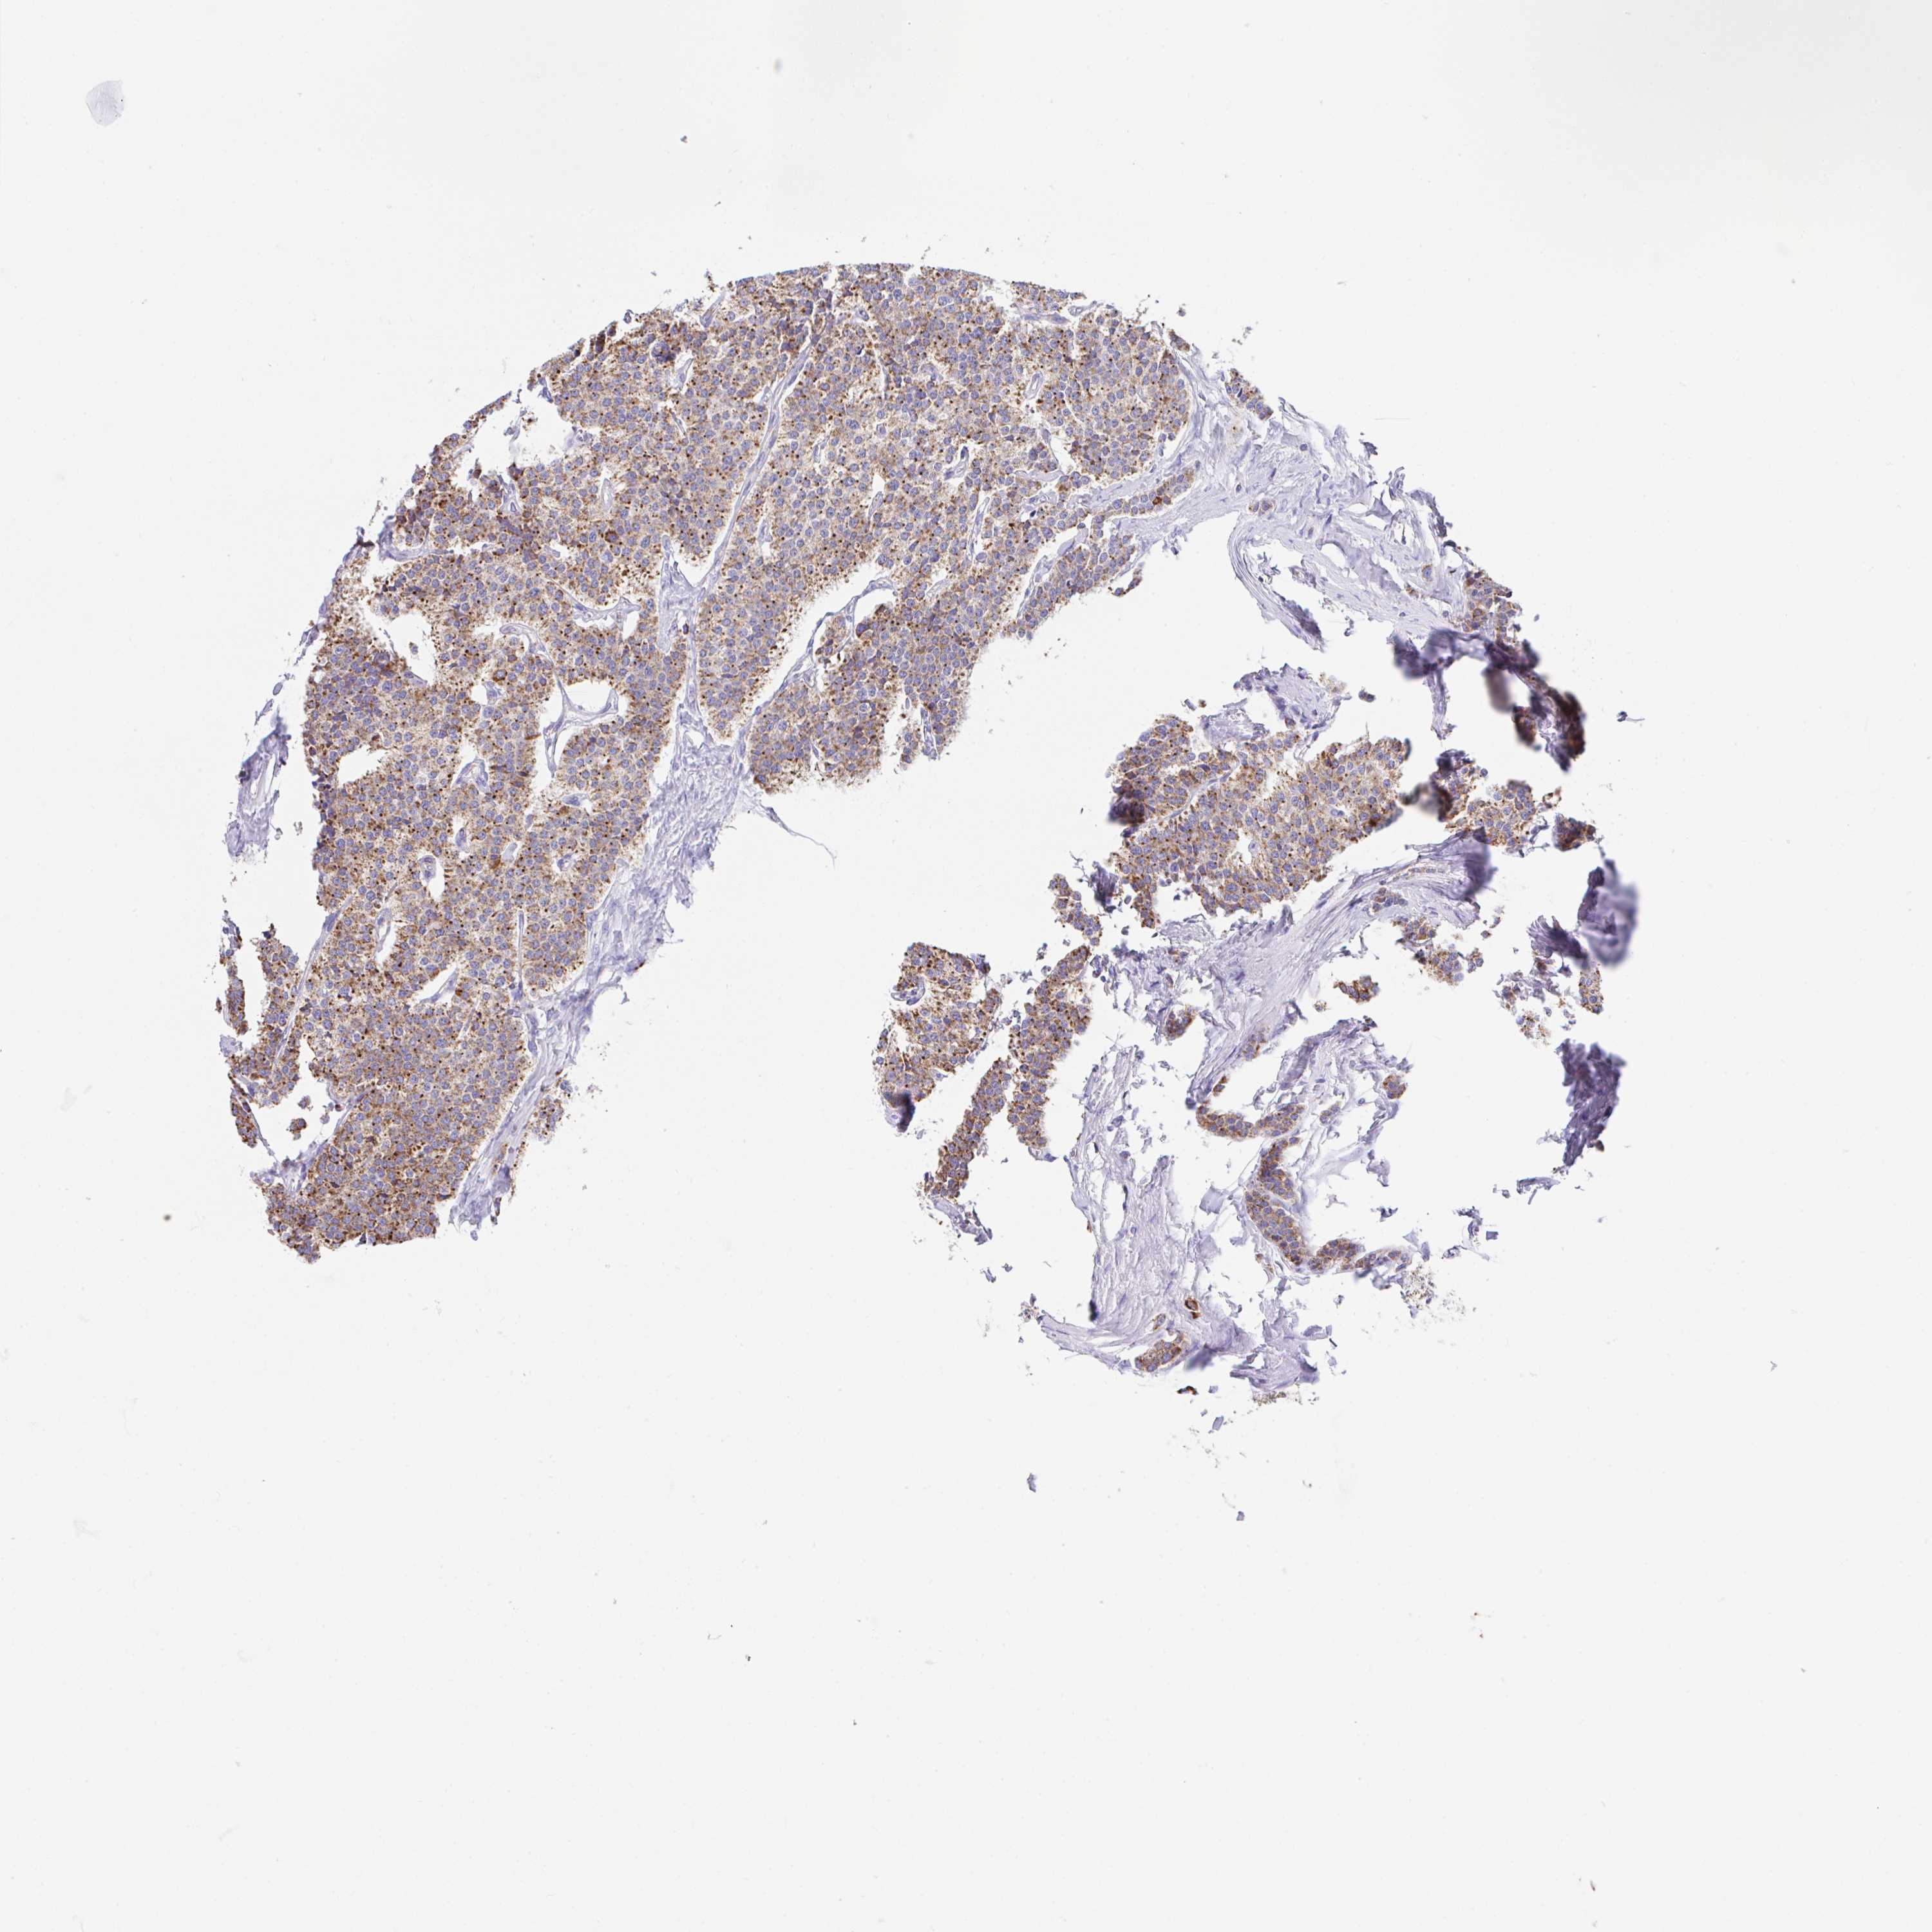

CARCINOID - Protein expressioni

A mouse-over function shows sample information and annotation data. Click on an image to view it in a full screen mode. Samples can be filtered based on level of antibody staining by selecting one or several of the following categories: high, medium, low and not detected. The assay and annotation is described here.

Antibody stainingi

Antibody staining in the annotated cell types in the current human tissue is reported as not detected, low, medium, or high, based on conventional immunohistochemistry profiling in selected tissues. This score is based on the combination of the staining intensity and fraction of stained cells.

Each image is clickable and will lead to virtual microscopy that enables deeper exploration of all samples and also displays staining intensity scores, fraction scores and subcellular localization as well as patient and tissue information for each sample.

Antibody HPA057849

Staining

Medium

Intensity

Moderate

Quantity

75%-25%

Location

Cytoplasmic/membranous

Carcinoid, malignant, NOS